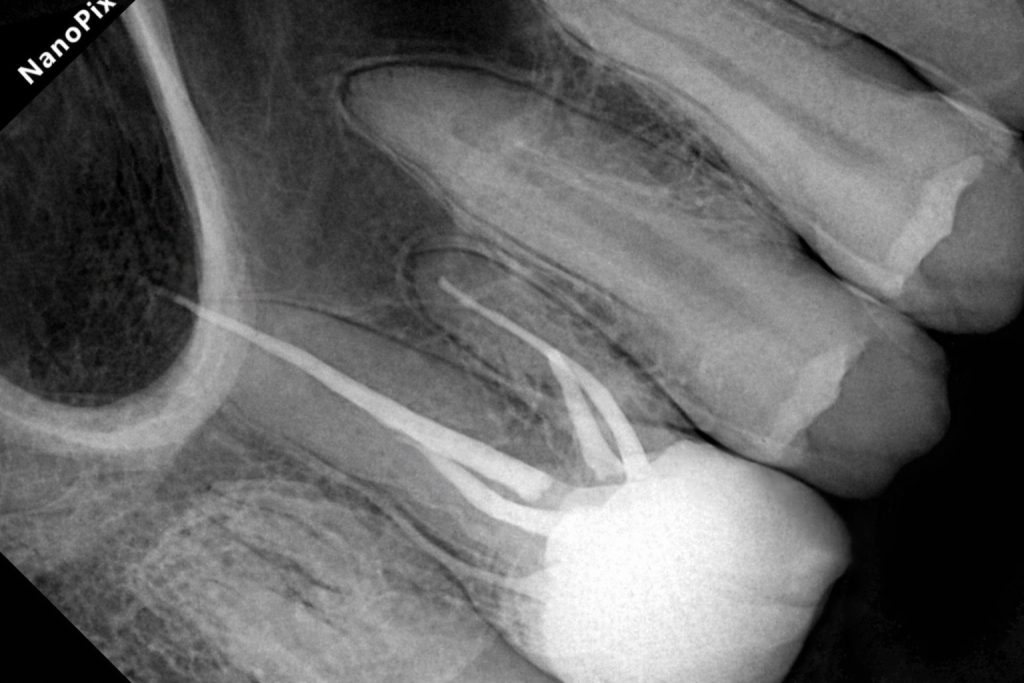

Obturation

Following drying of the canals, obturation was completed using gutta-percha with a bioceramic sealer to ensure a three-dimensional seal. A postoperative radiograph confirmed adequate length, density, and taper of the root fillings.

Outcome and Follow-Up

The final restoration demonstrated excellent marginal adaptation, anatomical form, and occlusal harmony. Postoperative radiographs confirmed a dense coronal seal over a well-executed root canal filling.